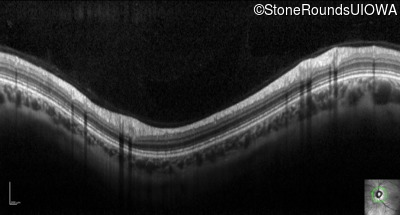

Optical Coherence Tomography - Right - 20/20 -1

Exemplar / OCT Stack